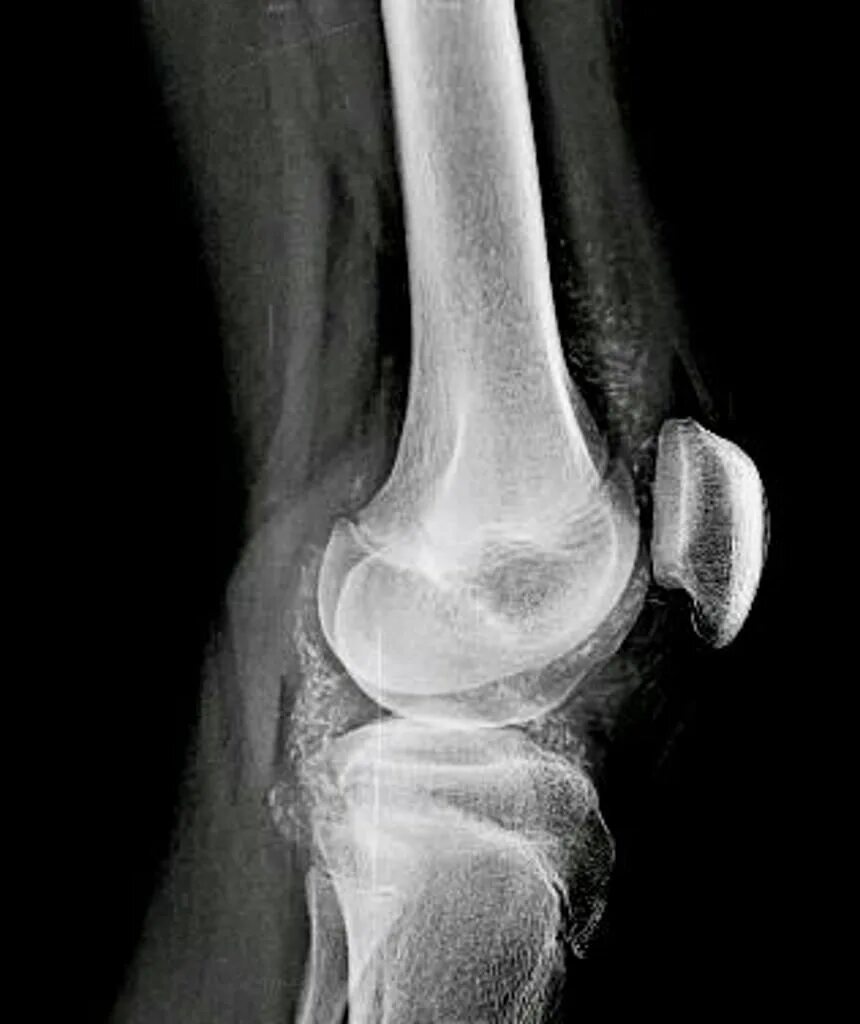

Обызвествление сухожилий мышц